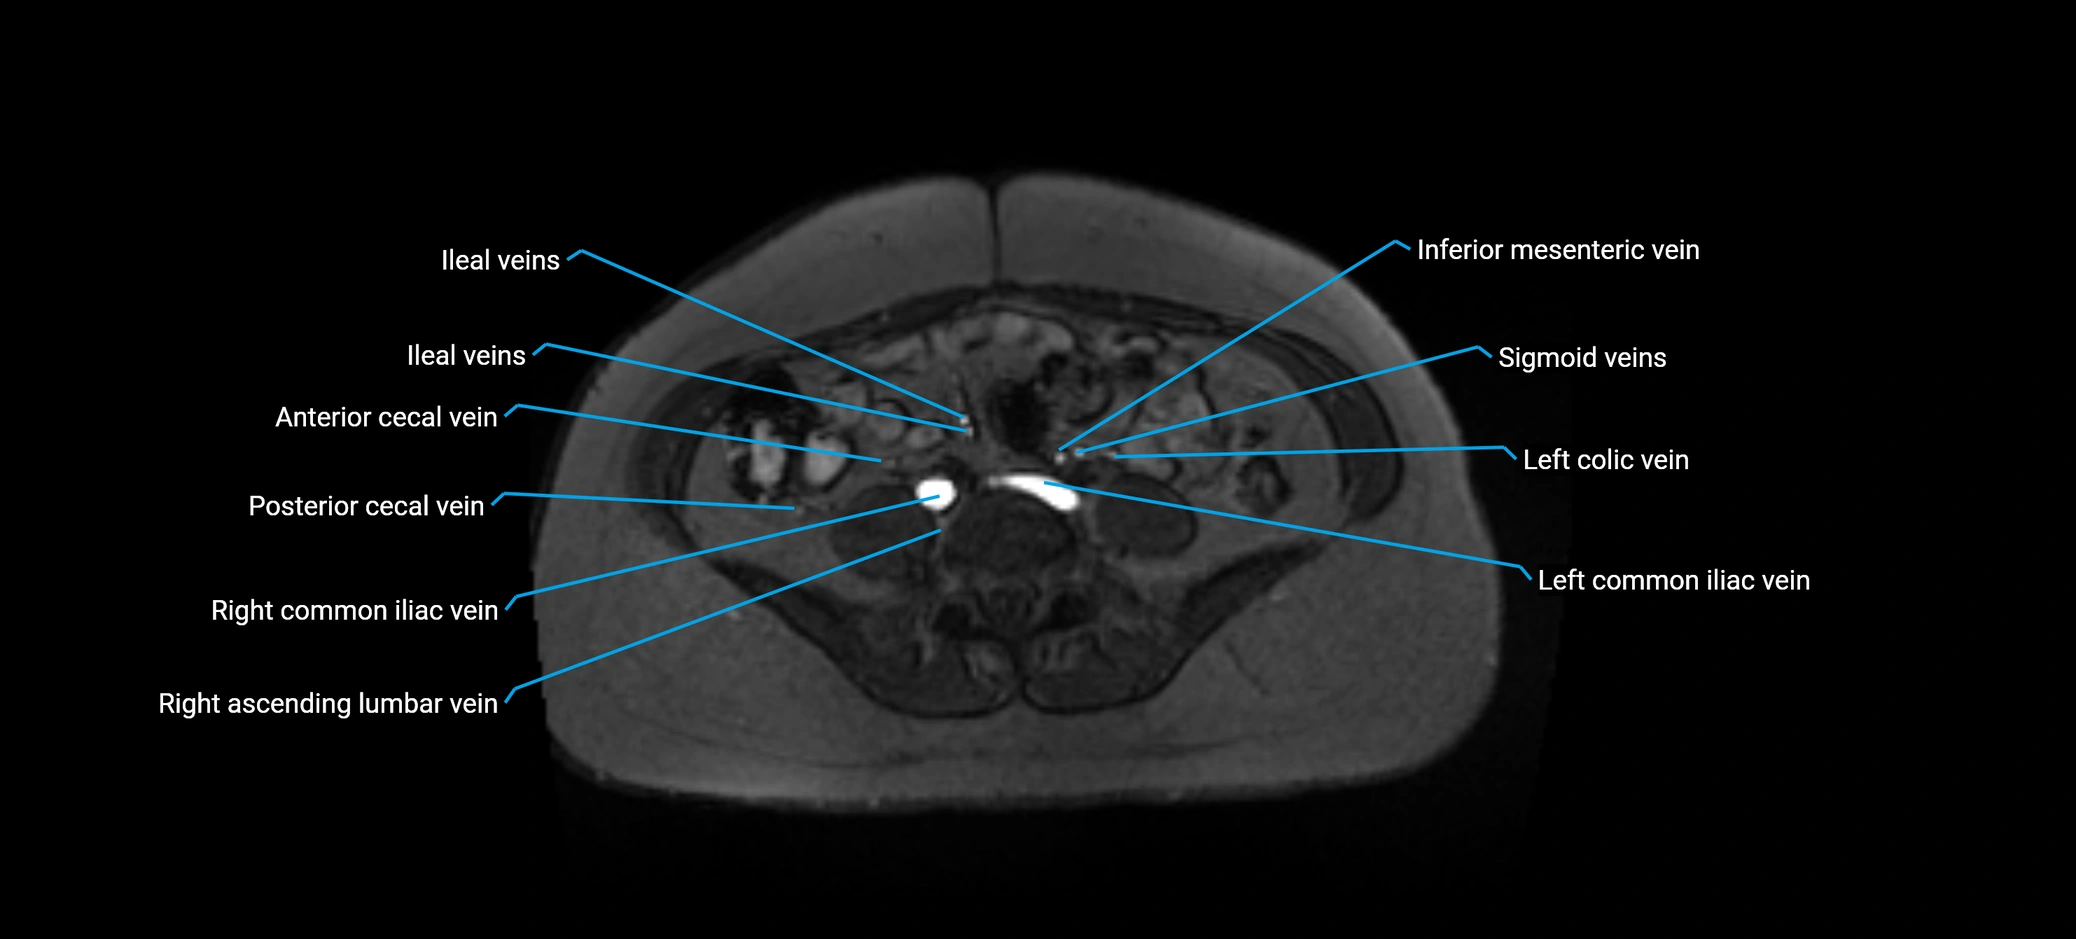

MRI image

image